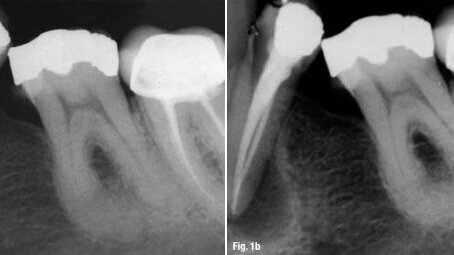

Figs. 1a & 1b : Un exemple de technique endodontique de haute qualité, dans lequel les impératifs biologiques n'ont pas été respectés : en dépit de la localisation et de la préparation du canal radiculaire secondaire, et de la condensation de l'obturation complète du système racinaire, les lésions associées à la dent ont augmenté en taille.